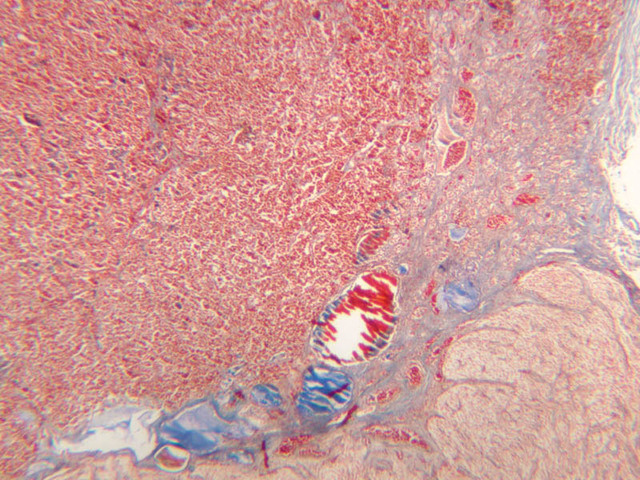

The adrenal gland (slide B-59, H&E [2.5x-labeled, 10x-labeled, 20x, 40x-labeled] [2.5x, 10x-labeled, 20x, 40x]; B-60, H&E [2.5x-labeled, 10x, 20x, 40x]; B-62, H&E [10x, 20x, 40x] [2.5x, 10x]) is a composite organ consisting of two functionally, structurally and embryologically different parts—an outer cortex and an inner medulla. Observe the gland at low power. Find the loosely organized tissue that comprises the medulla and the partially-separated columns of cells that make up the cortex. Scan the capsule and the tissue around it, looking for nerves and blood vessels. Study the pattern of cortical vasculature. In a pattern similar to that seen in the pars distalis of the pituitary, sinusoids run along the edges of columns or cords of cells. Owing to different arrangements of its constituent cells, the adrenal cortex has a layered appearance. From the capsule inward, these cortical layers are known as the zona glomerulosa, the zona fasciculata, and the zona reticularis.

The zona glomerulosa is located immediately beneath the capsule (B-60 adrenal gland, dog [10x, 20x] [20x, 40x]; B-59 [2.5x, 10x, 20x] [2.5x, 10x, 20x]). Its constituent cells are arranged in arcs or spheres, and, owing to their relatively small size, their nuclei appear to be close together. Cells of the zona glomerulosa secrete mineralocorticoids (e.g., aldosterone). The zona fasciculata consists of parallel columns or cords of cells that radiate toward the medulla and are separated by blood sinusoids (B-60 [2.5x, 10x, 20x, 40x]; B-62 [20x, 40x]). Owing to the extraction of lipids during histological processing, the cytoplasm of cells in the zona fasciculata appears highly vacuolated or "foamy". Cells of the zona fasciculata secrete glucocorticoids (e.g., hydrocortisone & cortisone) and some gonadocorticoids (weak androgens). The zona reticularis is the deepest cortical layer and lies adjacent to the medulla (B-60 [20x, 40x]; B-62 [20x, 40x]). It is characterized by irregular, interconnecting cords of cells which are separated by anastomosing capillary networks or sinusoids. Cells of the zona reticularis, which are smaller than those of zona fasciculata and do not contain as many lipid vacuoles, secrete gonadocorticoids and some glucocorticoids.

The medulla is composed of large epithelioid cells, arranged in small groups or cords which are separated by blood vessels. Usually, several large veins mark the center of the medulla. When fresh adrenal gland is incubated in solutions of chromium salts (as was the specimen on slide B-61), brownish precipitates form in the cells of the medulla-- hence, the name chromaffin cell (B-61, chromaffin [2.5x, 10x, 20x, 40x] [2.5x, 10x, 20x, 40x-labeled]). The more darkly stained chromaffin cells are known to contain norepinephrine, the less darkly stained cells, epinephrine. In essence, chromaffin cells are specialized postganglionic sympathetic neurons. How does the ultrastructure of these cells differ from that of the secretory cells of the adrenal cortex?